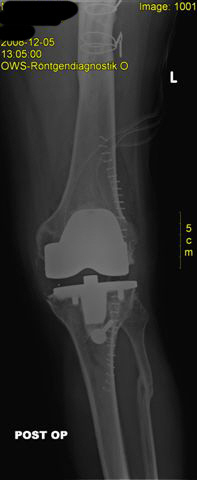

postoperatives Röntgen mit korrektem Sitz der Knieprothese

postoperativer Zustand mit liegender zementierter Knieprothese und gerade gestellter Beinachse